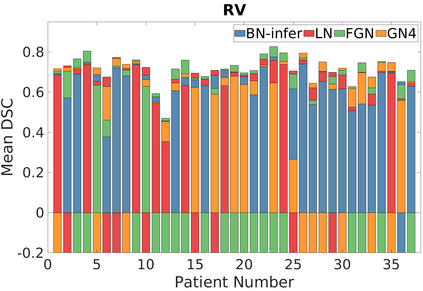

Deep Convolutional Neural Networks (DCNNs) are used extensively in biomedical image segmentation. However, current DCNNs usually use down sampling layers for increasing the receptive field and gaining abstract semantic information. These down sampling layers decrease the spatial dimension of feature maps, which can be detrimental to semantic image segmentation. Atrous convolution is an alternative for the down sampling layer. It increases the receptive field whilst maintains the spatial dimension of feature maps. In this paper, a method for effective atrous rate setting is proposed to achieve the largest and fully-covered receptive field with a minimum number of atrous convolutional layers. Furthermore, different atrous blocks, shortcut connections and normalization methods are explored to select the optimal network structure setting. These lead to a new and full-scale DCNN - Atrous Convolutional Neural Network (ACNN), which incorporates cascaded atrous II-blocks, residual learning and Fine Group Normalization (FGN). Application results of the proposed ACNN to Magnetic Resonance Imaging (MRI) and Computed Tomography (CT) image segmentation demonstrate that the proposed ACNN can achieve comparable segmentation Dice Similarity Coefficients (DSCs) to U-Net, optimized U-Net and hybrid network, but with significantly reduced trainable parameters due to the use of full-scale feature maps and therefore computationally is much more efficient for both the training and inference.